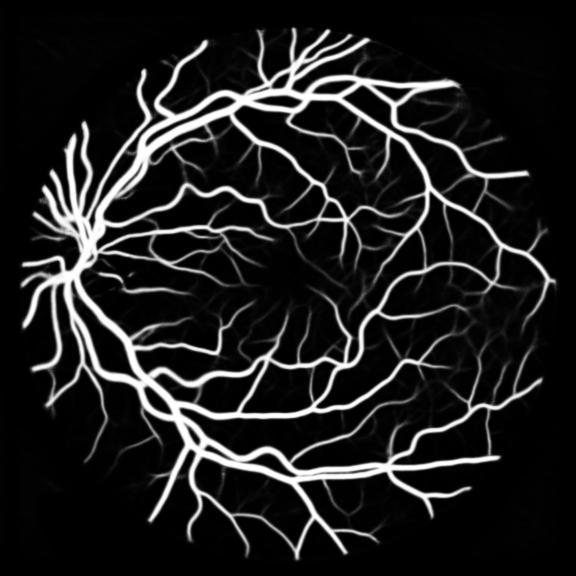

All three datasets are processed by subtracting the mean and normalizing according to the standard deviation. We use Adam optimizer, set the initial learning rate to 0.001 which is reduced by ten times if the training set loss does not drop during 10 consecutive epochs. We augment data using rotation, crop, flip, shift, change in contrast, brightness and hue. We set batch size to 4 for Skin Dataset and 32 for DRIVE and CHASE_DB1 whose patch size is relatively smaller. For each model we train 50 epochs and the result is shown in Table 1. Models with MixModule have better performance than those not and the best performance in each metric all comes from MixModule-based models. We also show some outputs of the networks in Figure 4.